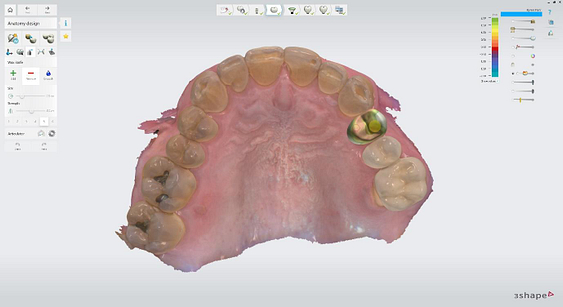

Implant detection matches the scan body in the intraoral scan with the digital library. A colour scale is given to show the accuracy of the matching (Green is good).

Digital impressions were captured using the TRIOS 4 intraoral scanner, and the implant-supported crown was designed using 3Shape Design Studio.